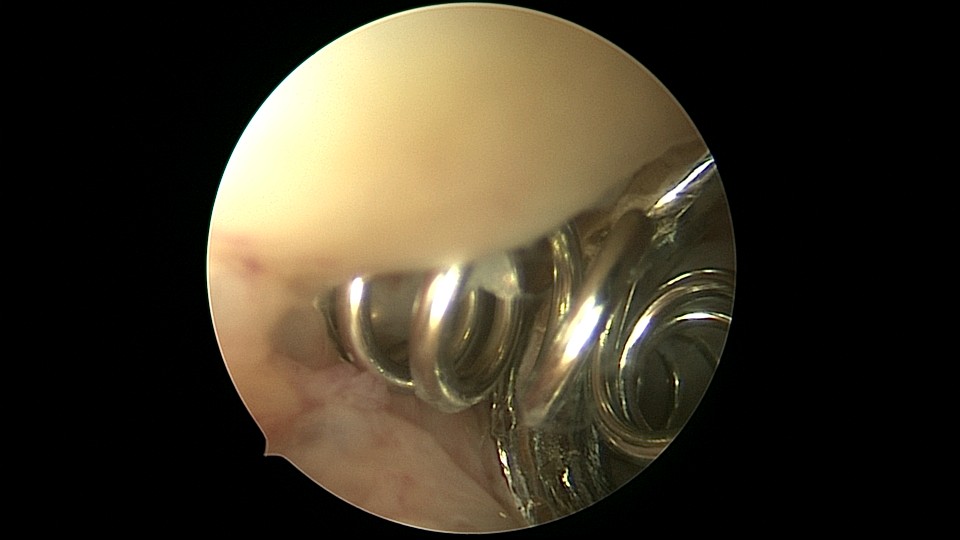

患者54岁,G1P1,剖宫产1次,安环30+年,绝经4年。40年前患者曾行左侧髋关节骨折手术,左下肢外展困难,患者肥胖,阴道很深,金属扩阴器和一次性扩阴器均无法暴露宫颈,用阴道内镜方式进入宫腔,但宫腔镜长度不够,远远能看见环,无法到达环的部位,再次试图暴露宫颈失败,用宫颈钳夹着阴道壁下拉,宫腔镜进入宫腔,但异物钳夹持力度不够,取出失败。用取环钩盲探沿宫腔镜外侧推挤进入宫腔,经历多次拧转,取环钩几乎向前弯成直角,直视下终于钩住节育环,掰直取环钩后缓慢拉出节育环,环变形。